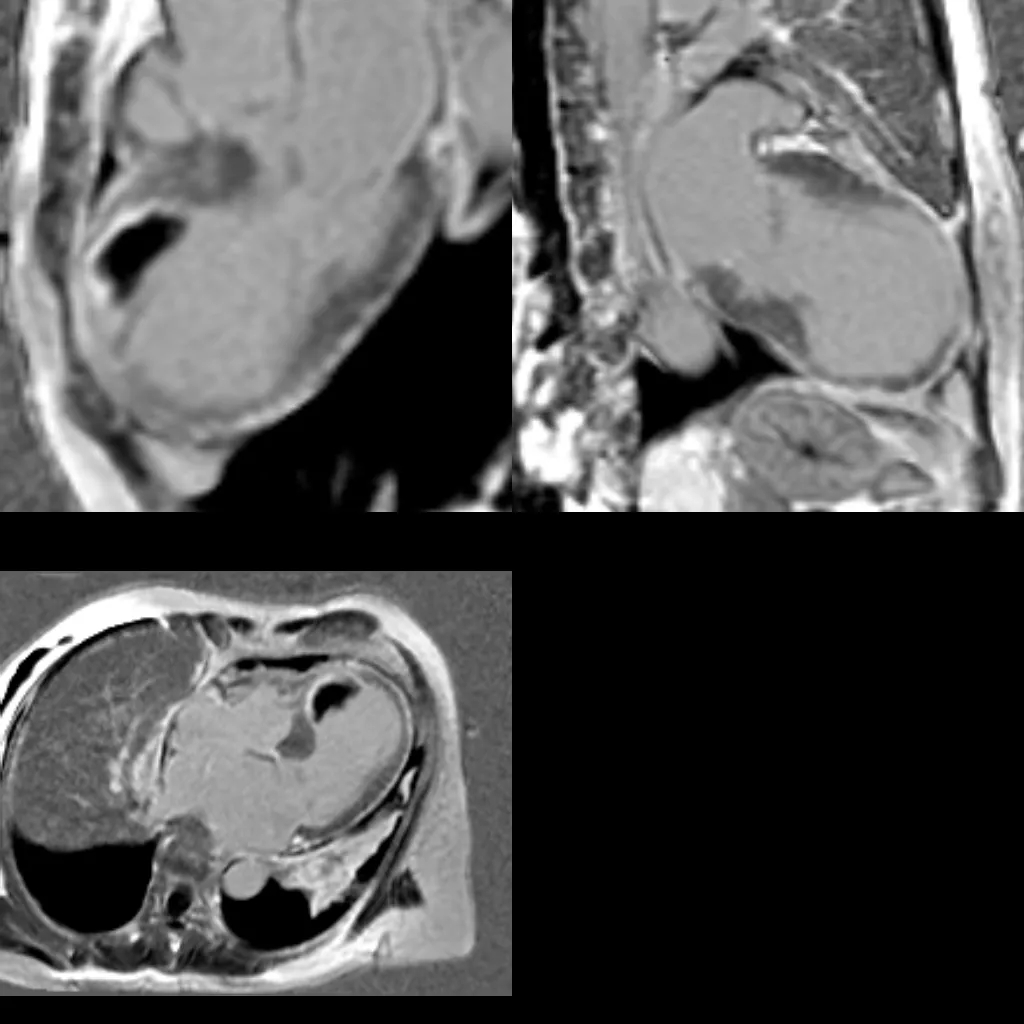

(3)核磁表现同时具备心肌梗死(室间隔基底段至心尖部心内膜下延迟强化)与应激性心肌病(“章鱼篓”样改变,且延迟强化未累及室壁瘤节段)的特征,考虑患者存在心肌梗死合并应激性心肌病。

基于以上3点及患者病史、临床症状等,推测发病过程可能为:急性心肌梗死诱发应激性心肌病,从而出现后续SAM征、流出道梗阻、ST段再次抬高等变化及心脏核磁提示“章鱼篓”样形态演变,均可视为在急性心肌梗死的基础上,应激进一步加重病情出现一系列并非心肌梗死的变化。由于需证明室壁异常运动的可逆性,目前还无法明确就诊,需进一步随访3个月。